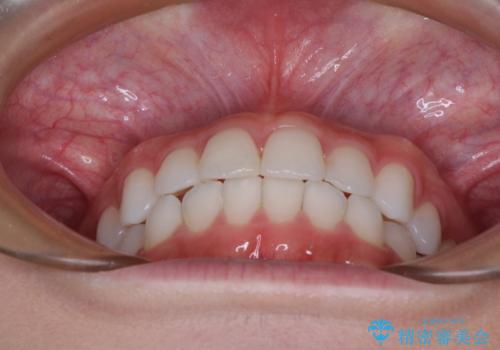

- 歯並びと虫歯をきれいにしたいとのことで来院された患者様です。

楽して短期間で歯列を整えたいとのことで、ワイヤー装置を用いて矯正治療を行い、矯正治療後に下顎の虫歯はセラミックインレー、上顎はPGAインレー(ゴールドインレー)、根管治療を行う歯についてはオールセラミッククラウンにて補綴治療を行うこととしました。

- 費用(概算)

矯正治療は8ヶ月ほどで終了し、速やかに虫歯治療に移行することができました。

保険治療で用いる樹脂(コンポジットレジン)で行った虫歯治療は、周辺が変色して汚くなっていましたが、下顎はセラミックインレーで審美的に、上顎はPGAインレーで歯に負担の少ない治療を行うことができました。